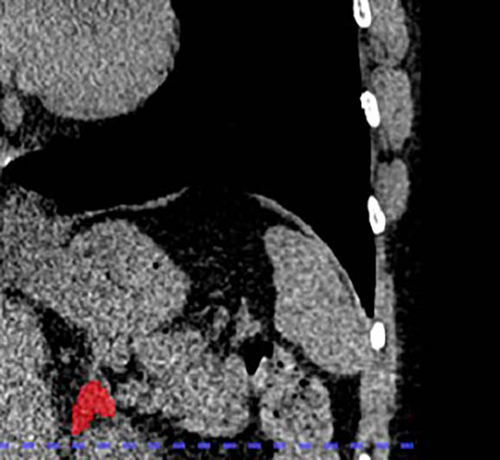

Figure 3. Right adrenal automated 2D segmentation in chest CT.